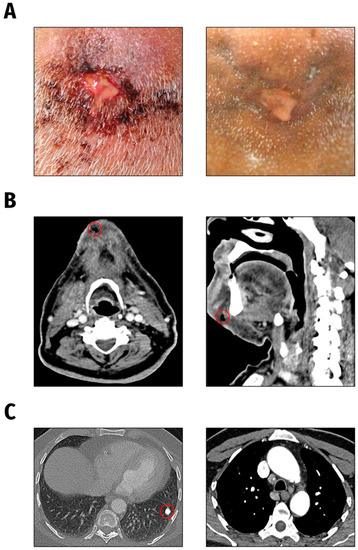

3.1. Strain Origin and Clinical Background